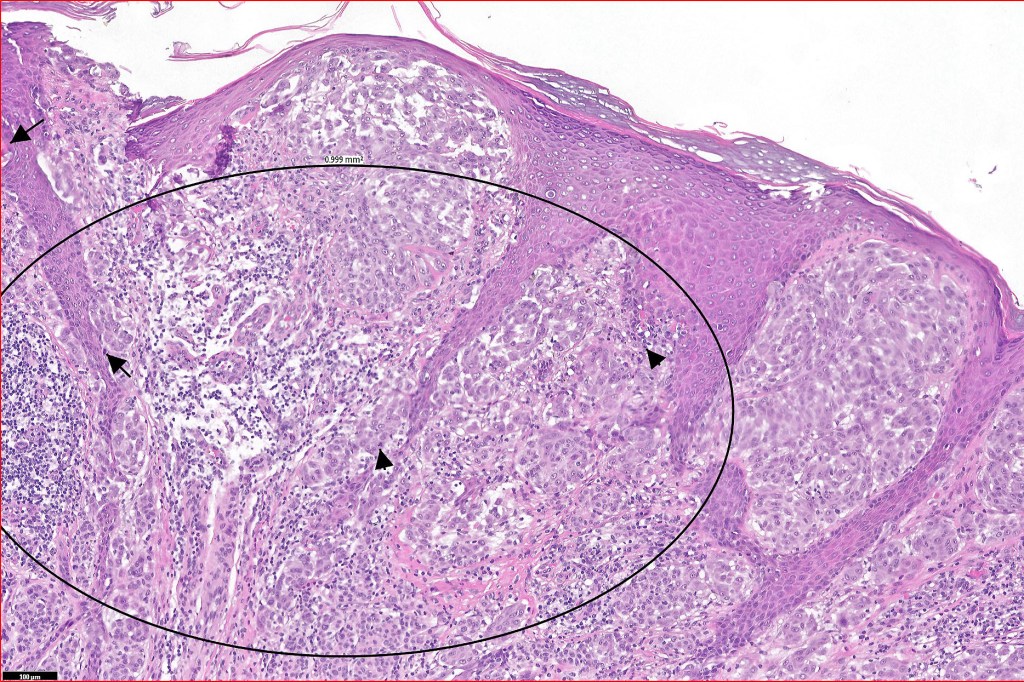

Histological features

•Asymmetrical, poorly circumscribed

•May show effacement/consumption of epidermis or ulceration

•Peripheral Pagetoid spread

•Large nodules which often show impaired maturation